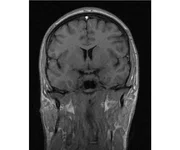

делал в обласной на siemense.В заключении выданом мне через 15мин.после мрт (легкая дегидрация)

Меня смутил факт выдачи заключения через 10мин(наверно они у них зарание напечатаные)я не медик.достаточно мимолётного взгляда на снимки?А вы видете на них гидроцефалию? Я лиш спросил куда идти с результатами томографии?и не хотел никого роздражать.

Я попросил взглянуть на снимки и сказать видна.ли на них гидроцефалия?или куда обратится за консультацией по этому вопросу?В мрт снимках наверно розбирается любой нервопатолог(я так предположил)

Я уже говорил, что независимо от того, есть на МРТ гидроцефалия или нет, лечиться тебе нужно только в том случае, если есть какие-либо проявления болезни, иначе на все эти анализы можешь забить... Но давай все-таки разберемся с томограммой.

Итак, с самого начала томограмма обозначала срез какого-либо органа на определенной глубине, позволяла заглянуть вовнутрь. При компьютерной томографии аппарат делает десятки срезов головного мозга в разных направлениях и из этого множества срезов он моделирует полноценное объемное изображение мозга в натуральную величину. Обрати внимание, компьютер работает не с этими миниатюрными изображениями, а с трехмерной моделью в масштабе 1:1. Эту модель вдоль и поперек анализирует суперсовременный компьютер, выполняющий миллионы операций в секунду. Только ***** может пытаться перепроверить компьютер, ведь человеку не хватит всей жизни чтобы проанализировать то, что компьютер с тобой сделал за 10 минут. Я хочу, чтобы ты это понял!

Ты разместл здесь несколько миниатюр и хочешь, чтобы врач по ним создал полноценное объемное изображение в натуральную величину, а потом осмотрел его со всех сторон и дал заключение? Но ведь это невозможно. Это просто насмешка над врачом, это издевательство над здравым смыслом. Принеси Букеру уменьшенный в 50 раз снимок зуба и спроси у него, в каком состоянии там корневые каналы. Или давай я дам тебе скрин со спутниковой карты города и попрошу тебя описать, какого цвета и какой модели запечатленная со спутника машина, какой у нее гос.номер, сколько в ней пассажиров, сколько из них мужчин и сколько женщин...

Надеюсь, ты понимаешь, что это невозможно. И воссоздать по приведенным тобой аватарам полную картину мозга тоже невозможно. Пойми, если уж называть вещи своими именами, то ты запостил полнейшую ***ню! Ты не хотел никого обидеть, ты ведь сам не ведал, что творил. Ты продемонстрировал полнейшую медицинскую безграмотность и полное невежество, но претензий к тебе нет. Ты ведь не один такой. Ты пожелал того, что сделать невозможно, и тут же у тебя нашлась сочувствующая, некая П., которую, по большому счету, надо бы послать в П., коль уж она считает, что врач должен тут сделать немедленно и бесплатно то, что делает немецкий компьютерный томограф ценой в миллионы долларов.